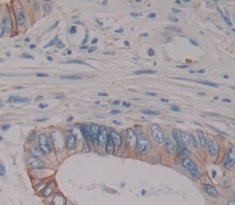

Polyclonal Antibody to Matrix Metalloproteinase 16 (MMP16)

Product No.: PAB533Hu01

Organism species: Homo sapiens (Human)

Monoclonal Antibody to Matrix Metalloproteinase 16 (MMP16)

Product No.: MAB533Hu22

Organism species: Homo sapiens (Human)